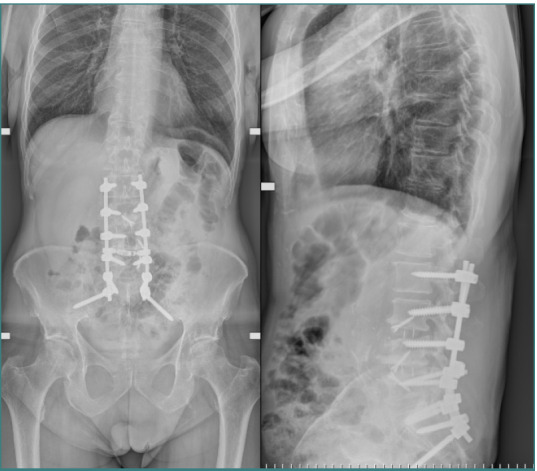

Vascular injuries during anterior lumbar interbody fusion (ALIF) are reported in the existing literature with an incidence rate ranging from 1% to 24%, predominantly venous lacerations owing to branch vessel avulsions during mobilization and retraction. Arterial injuries, although less frequent, occur at an incidence of 0.45% to 1.5% and are mainly characterized by thromboses; aortic lacerations remain exceptionally rare. L4-L5 and L5-S1 are the two levels associated with the majority of vascular complications. Preoperative 3D CT angiography is paramount and a gold standard, as it illustrates the anatomic variations of the iliolumbar vein, the aorta, and the vena cava bifurcation, providing the surgeon with valuable information regarding operative trajectories. Regarding preventive measures, venous laceration, the most common vascular injury, occurs less frequently when employing nonthreaded interbody grafts such as iliac crest autograft or femoral ring allograft. Also, left iliac artery thrombosis can be decreased intraoperatively by intermittent release of retraction. Managing vascular complications includes compression for bleeding control, Trendeleburg positioning of the patient and venorrhaphy, and the employment of topical clot-forming enhancement and/or hemostatic agents. Although postoperative lower limb duplex ultrasonography can be an effective tool, magnetic resonance venography (MRV) and intravenous catheterization (IVC) remain the gold standards for diagnosing postoperative pelvic vein thrombosis in cases of iliac vein repair after anterior spine surgery. This paper aimed to highlight the incidence of major vascular injury during ALIF surgery, describe predisposing risk factors, and discuss management techniques while highlighting the requirement for more sensitive and factor-specific studies to attain a more profound understanding of the mechanism of vasculature complications during ALIF procedures.